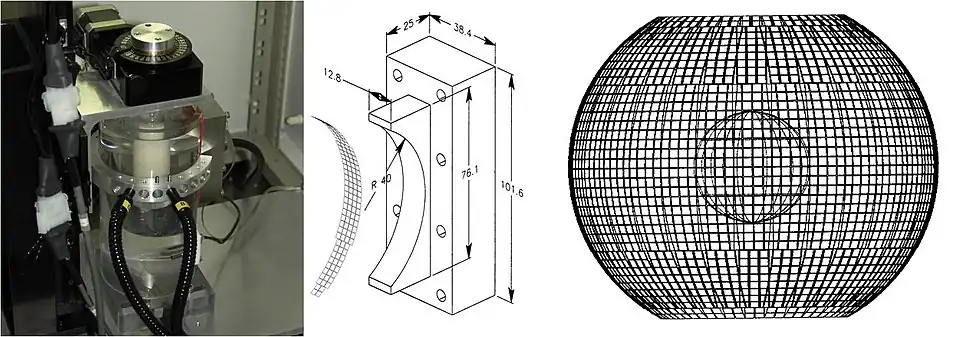

In order to capture sufficient thermoacoustic data to form an accurate 3D map of electromagnetic absorption, it is necessary to surround the anatomy being imaged with a 2D array of transducers. The world's first 3D thermoacoustic animal scanner (Fig. 8: left panel) accomplished this by combining a cylindrical array of 128 transducers (Fig. 8: center panel) with rotation of the animal being imaged about the vertical axis. The net result was to capture thermoacoustic data over the surface of a sphere surrounding the animal being imaged (Fig. 8: right panel).[21] This device was capable of visualizing structures as small as 1/3 millimeter. An animated 3D image of the vasculature in the head of a mouse is displayed in Fig. 9. This animated image was acquired using near infrared radiation at 800 nm, where optical absorption by blood is higher than surrounding tissues. Therefore, the vasculature is preferentially visualized.